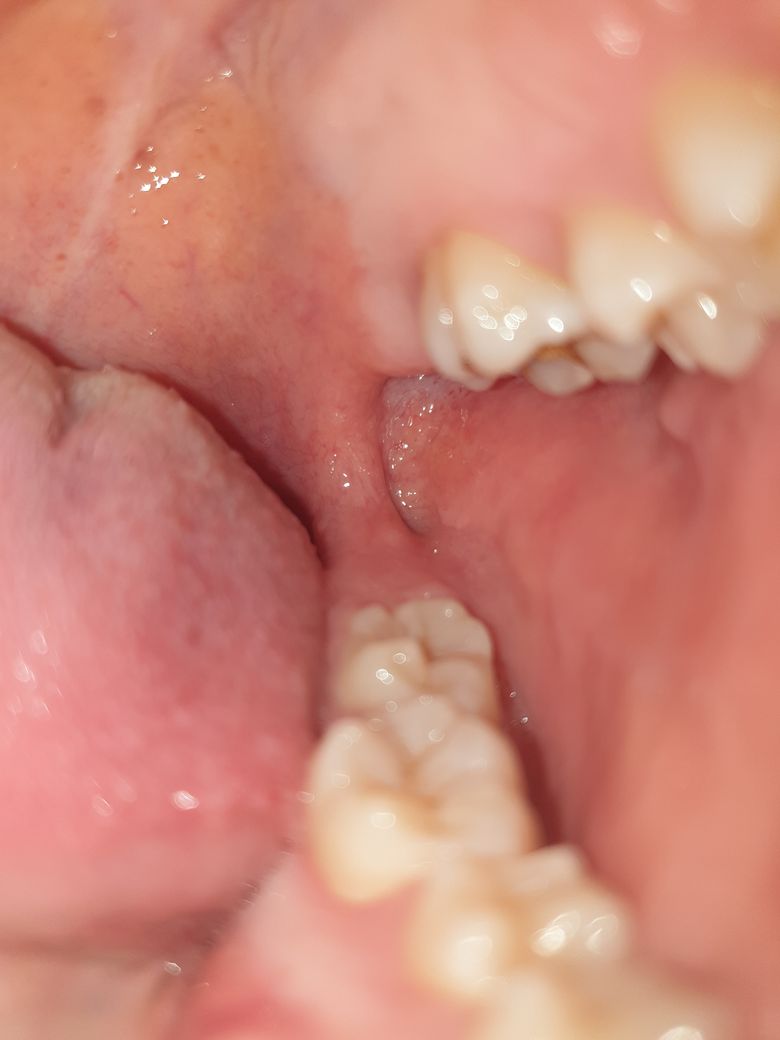

안녕하세요. 며칠 전부터 입 내부에 뭐가 생겼는데 닿으면 아프네요 깨문 기억도 없고 깨물 수도 없는 부위 같은데 왜 생긴 걸까요 ㅜㅜ 단순한 외상인지 다른 질병인지 궁금합니다!

현재 사진으로 보아서는 구내염일 가능성이 매우 높아 보입니다. 구내염은 여러가지 원인에 의해 나타나게 되며 교합이상, 외상, 음식물에 의한 자극 ,마찰 등에 의해서도 나타날 수 있습니다. 단순 구내염이라면 2주 이내에 회복되는 성질이 있으나 2주가 지났는데도 증상이 호전되지 않는다면 치과 방문 후 감별진단을 받아보셔야 합니다.